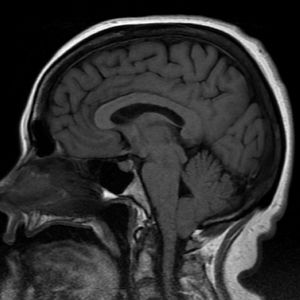

The 17 year old who was having occipital headaches, loss of balance, memory loss, tingling in hands and arms and fainting was diagnosed with Chairi Malformation type 1 or Arnold Chairi Malformation. A condition in which the brain tissue extends into the spinal canal. Can be present at birth or develop as the person grows. Treatment usually consists of Laminectomy or Decompressive craniectomy or monitoring.